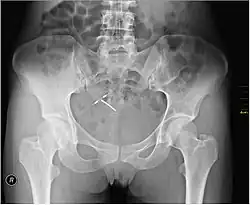

An intrauterine device (IUD), also known as an intrauterine contraceptive device (IUCD or ICD) or coil,[3] is a small, often T-shaped birth control device that is inserted into the uterus to prevent pregnancy. IUDs are a form of long-acting reversible contraception (LARC).[4]

Most copper IUDs have a T-shaped frame that is wound around with pure electrolytic copper wire and/or have copper collars (sleeves). The arms of the frame hold the IUD in place near the top of the uterus. The Paragard TCu 380a measures 32 mm (1.26") horizontally (top of the T), and 36 mm (1.42") vertically (leg of the T). Copper IUDs have a first-year failure rate ranging from 0.1 to 2.2%.[46] They work by damaging sperm and disrupting their motility so that they are not able to fertilize an egg. Specifically, copper acts as a spermicide within the uterus by increasing levels of copper ions, prostaglandins, and white blood cells within the uterine and tubal fluids.[6][47] The increased copper ions in the cervical mucus inhibit the sperm's motility and viability, preventing sperm from traveling through the cervical mucus, or destroying it as it passes through.[48] Copper can also alter the endometrial lining, and while studies show that this alteration can prevent implantation of a fertilized egg ("blastocyst"), it cannot disrupt one that has already been implanted.[49]

Advantages of the copper IUD include its ability to provide emergency contraception up to five days after unprotected sex. It is the most effective form of emergency contraception available.[50] It works by preventing fertilization or implantation but does not affect already implanted embryos.[49] It contains no hormones, so it can be used while breastfeeding, and fertility returns quickly after removal.[51] Copper IUDs also last longer and are available in a wider range of sizes and shapes than hormonal IUDs.[9] Disadvantages include the possibility of heavier menstrual periods and more painful cramps.[6]